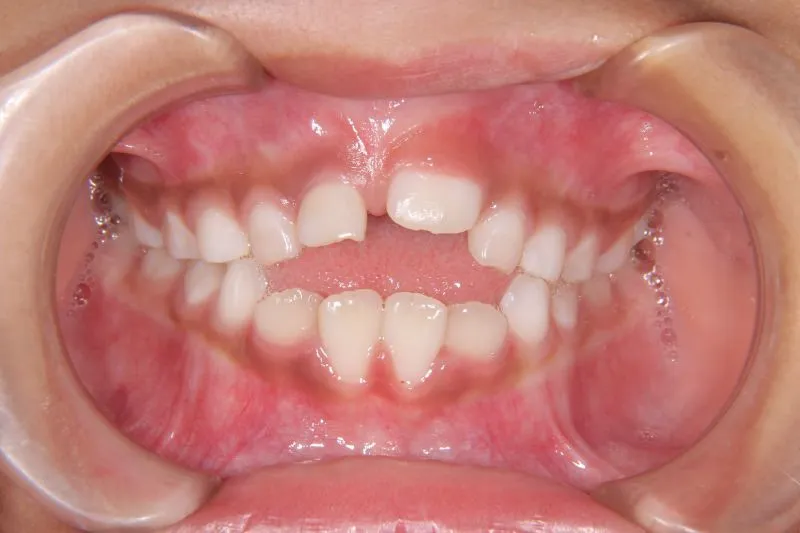

状態 前歯で噛めない(開咬/オープンバイト)

1.主訴 前歯がかみ合わない・出っ歯

2.診断名あるいは主な症状 開咬

前歯がかみ合っていません。

前歯は物を噛みちぎる(ハサミのような)役割をするのですが、歯と歯が離れていて本来の役割を果たしていません。

硬いものが嫌いな方や、噛むことが苦手な方に見受けられます。このまま、噛まずにいると

将来歯が残りにくくなります。

適切な治療を受ける必要があります。